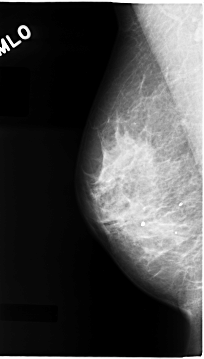

C_0065_1.LEFT_MLO

LEFT_MLO LINES 4704 PIXELS_PER_LINE 2552 BITS_PER_PIXEL 12 RESOLUTION 50 OVERLAY